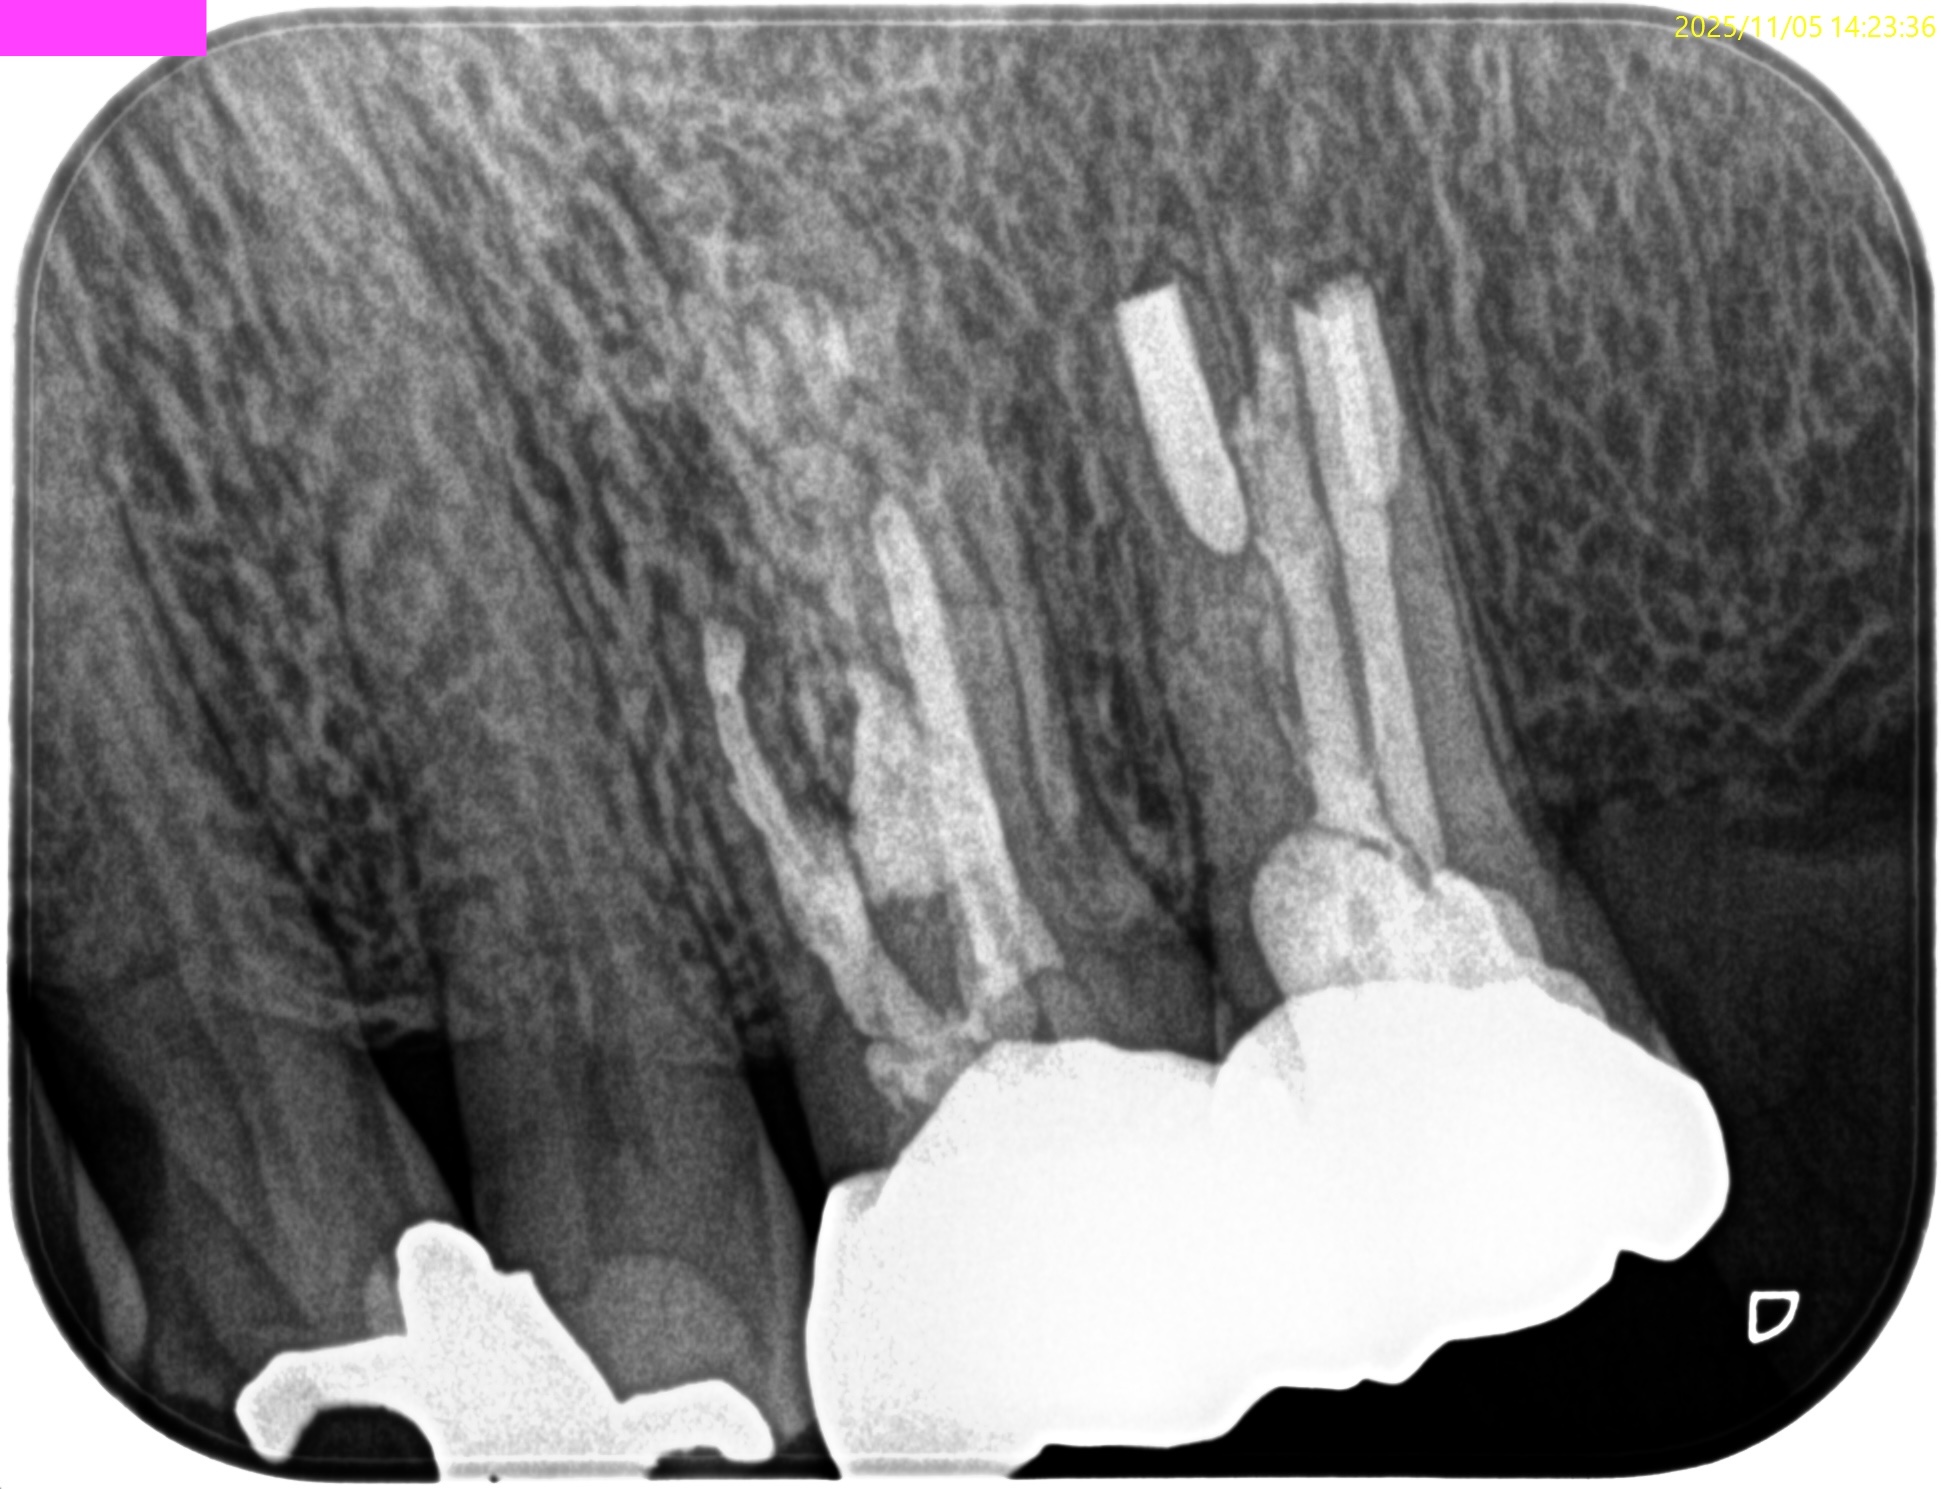

PA(2025.11.5)

治療前/直後と1年後を比較した。

完治だ。